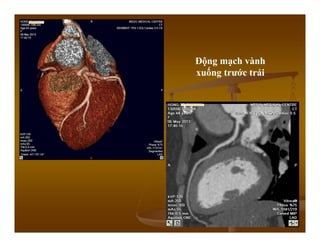

Động mạch vành phải

Động mạch vành

xuống trước trái

Hẹp 80% LAD